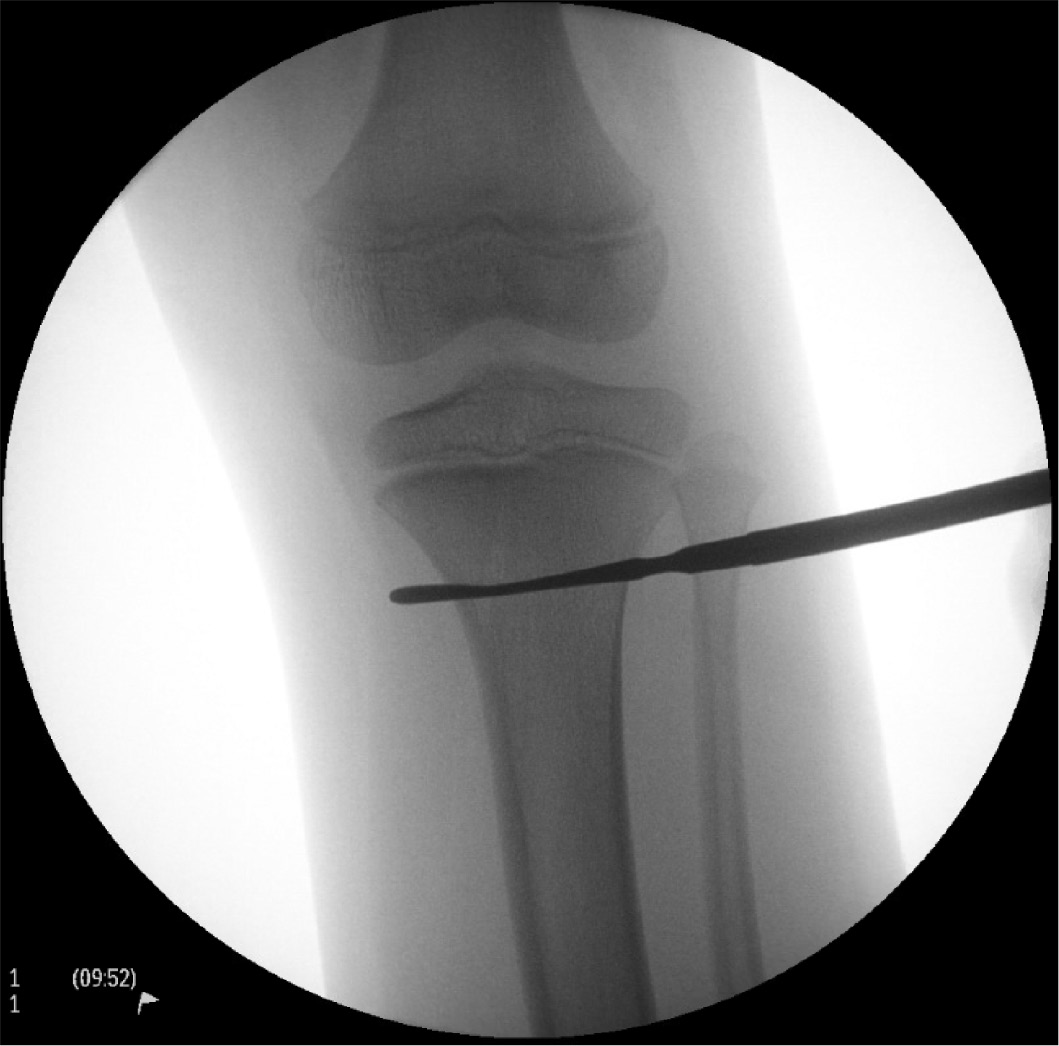

- Localize incision and insertion points fluoroscopically

- On AP fluoroscopy, place freer-elevator over proximal tibia to locate and mark medial and lateral incision points (see image below).

- Goal is to make start point lie within proximal metaphyseal flair, ~2 cm distal to proximal tibial physis.